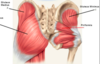

Label the muscles on this diagram.

Label this diagram.